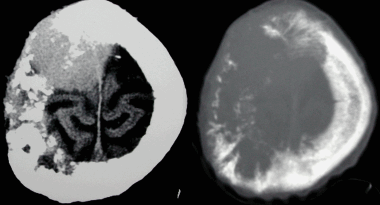

(Слева) Бесконтрастная КТ, аксиальный срез: определяется дольчатое гиперденсное объемное образование, расположенное по ходу намета мозжечка справа.

(Справа) МРТ, FLAIR, аксиальный срез: у этого же пациента визуализируется гипоинтенсивное многодольчатое объемное образование с перифокальным отеком и масс-эффектом на IV желудочек.